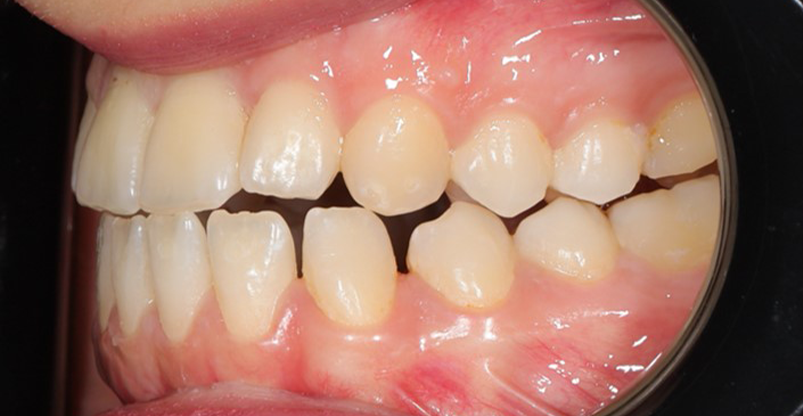

A 22-year-old female patient presented with a Class III malocclusion. She does not like her own profile. Her facial profile was straight with a slightly retrusive maxilla, the upper incisors were within normal inclination, and the lower incisors were retroclined. Bolton discrepency is on mandible for 6 teeth. A retruded upper lip and a normally positioned lower lip were noted. There was also a marked lack of midface support, and the constricted dental arches resulted in a narrow smile and pronounced dark buccal corridors.

At the end of treatment, the patient’s occlusion was corrected to Class I molar and canine relationships with a physiological overjet and overbite. Irregularities in both arches were eliminated, arch forms were coordinated, and incisor torque was effectively controlled to position the roots centrally within the alveolar bone, enhancing stability. Satisfactory intercuspation was achieved in both the anterior and posterior segments, with maintenance of midline coincidence and periodontal health throughout treatment. The case was finished and transitioned into the retention phase using fixed retainers in the maxillary and mandibular anterior regions.